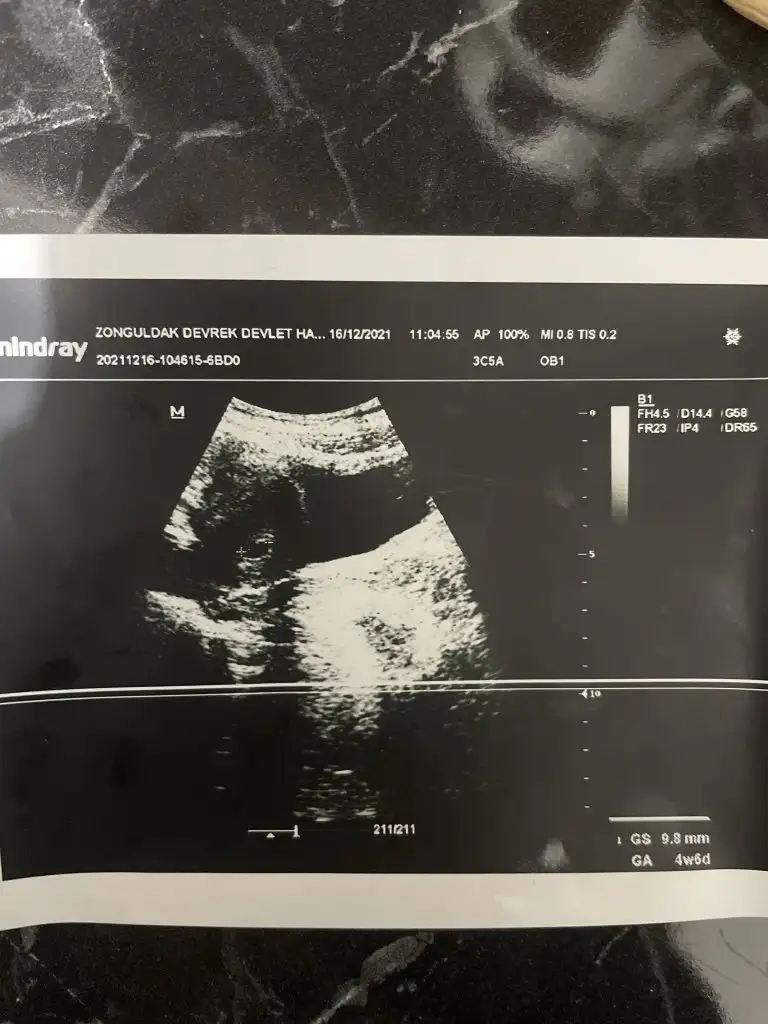

Allah razı olsun canim bebek iyi çok şükür gunde 3 kez progestan verdi agir bi is yapma dinlenmeye çalış ilişki olmasın dedi

Bu ara biraz dinlenmeyle geçirirsin bol bol su tüket oda önemli.. Parogestanı da önem amaçlı vermiştir